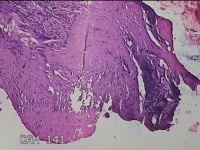

右耳前瘘管

性别

男

年龄

53岁

临床诊断

一般病史

反复右耳前红肿、流脓2月。

标本名称

大体所见

灰白暗红色组织.3x0.8x0.3cm一块,表面糜烂,切面灰白暗红色,质中。